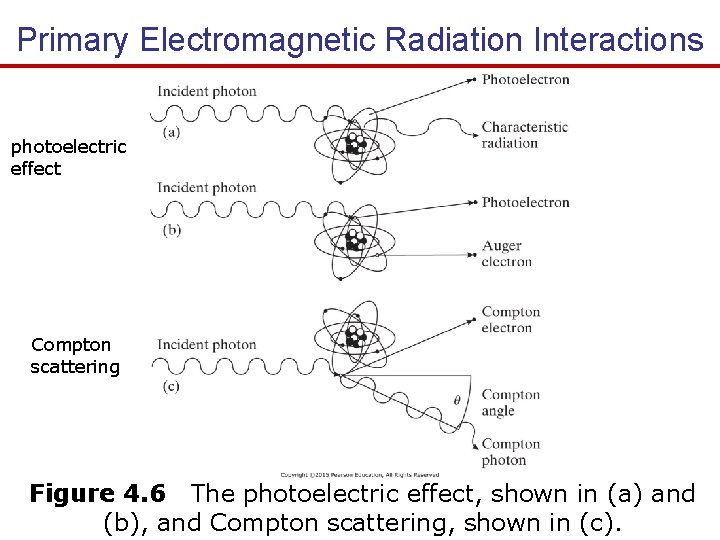

Primary Electromagnetic Radiation Interactions The three main mechanisms by which EM ionizing radiation interacts with materials to from images are: 1. The photoelectric effect - Incident x-ray photon totally loss energy to the atom’s electron cloud. - Provide contrast between different types of tissues in the medical image. 2. Compton scatter - Incident x-ray photon partially loss energy to the atom’s electron cloud and change direction. - Limit the resolution of x-ray images. 3. Pair production (need high energy 1. 02 Me. V so it isn’t applicable in medical imaging 25 - 500 ke. V).

Primary Electromagnetic Radiation Interactions photoelectric effect Compton scattering Figure 4. 6 The photoelectric effect, shown in (a) and (b), and Compton scattering, shown in (c).